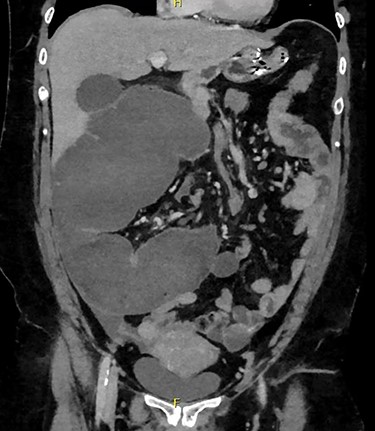

Admission blood tests were unremarkable. Abdominal X-ray showed non-specific signs of large bowel obstruction (Fig. 1). Computed tomography (CT) scan indicated unusual location of the caecum in the right upper quadrant along with gross distension up to 13 cm (Fig. 2), a whirling pattern of mesenteric vessels (Fig. 3) and a competent ileo-caecal valve. In context of her surgical history, these findings raised concern for a closed loop obstruction due to internal herniation.